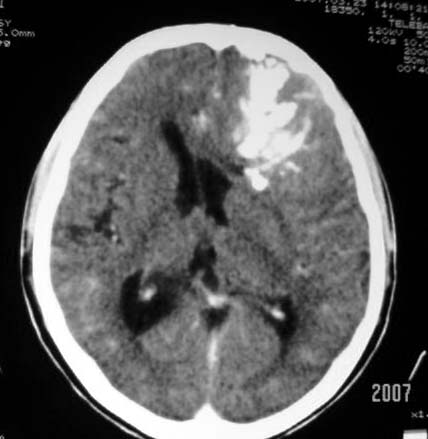

标题: CT7268:左额顶部病变增强片. [打印本页]

标题: CT7268:左额顶部病变增强片.

比较典型的少枝胶质细胞瘤ct表现,局部额骨垂直板有侵蚀变薄。

左额叶病灶内条片状高密度是钙化吗?是的话考虑少支胶质瘤可能大。不然有脑血畸形伴出血可能。

左侧额顶叶有条带状钙化的不规则形占位,增强呈不均匀轻度强化,局部颅骨受侵蚀变薄,典型的少支胶质细胞瘤。

比较典型的少枝胶质细胞瘤ct表现,局部额骨垂直板有侵蚀变薄